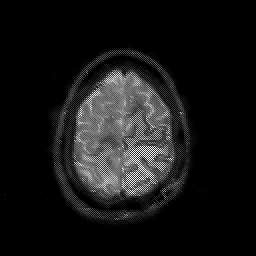

Glioblastoma multiforme overlay -- Slice #43

[Home][Help][Clinical][Tour 1][Tour 2][Tour 3] Slice 43